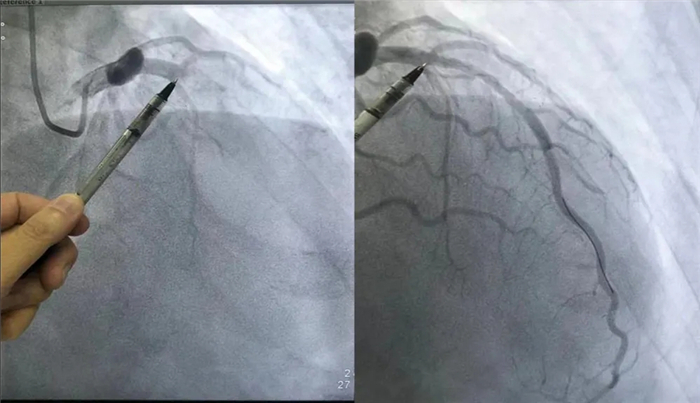

冠状动脉造影,术前术后对比图

科主任曾海、护士长明玲、导管室护士长吴凤丽,带领团队精诚协作。他们及时将患者送入导管室行冠状动脉造影,手术发现冠状动脉前降支急性闭塞,前向血流“0”级;当即在冠状动脉腔内注入尿激酶原、欣维宁反复交替行溶栓治疗,冠状动脉腔内反复多次行抽吸血栓术,抽出大量红色血栓块,冠状动脉腔内血流恢复灌注,前向血流3级;手术成功挽救了患者生命,患者生命体征平稳安全返回病房。